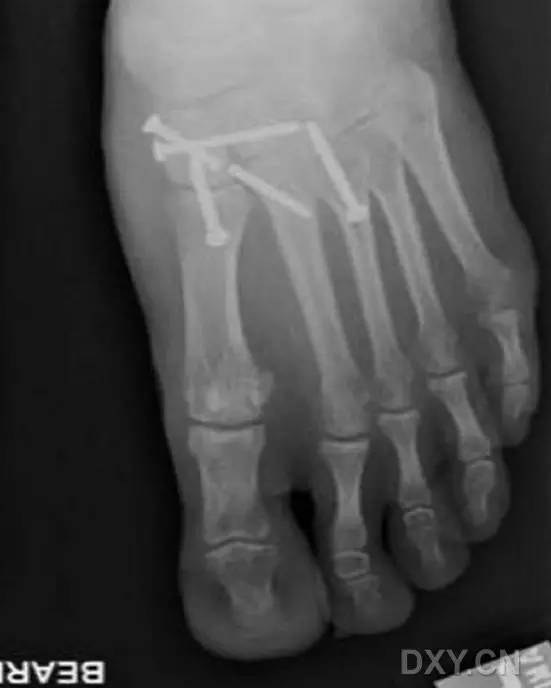

完成术区暴露和维持复位后,在 X 线透视下,自足底方向经第 2 跖骨基底背外侧向内侧楔骨置入导针,采用空心钻经导针钻孔,然后将一枚 4.0-5.0 mm 直径适当长度的半螺纹空心螺钉经导针置入(图 4)。

图 4. 术中 X 线透视下,经第 2 跖骨基底背外侧向内侧楔骨置入 Lisfranc 螺钉

最后,处理第 1 跖楔关节不稳等其他损伤情况。对于其他损伤可采用关节外固定技术进行处理(图 5),相关技术细节,可参考其他相关文献,在此不再赘述。

图 5. 术前 X 线片和透视观察显示,第 2 跖骨基底骨折伴第 1 跖楔关节不稳(A、B)

采用本文介绍的 Lisfranc 螺钉固定技术和关节外内固定技术进行损伤进行固定治疗。术后 3 年随访表明,原损伤部位复位、固定位置良佳,几乎无明显皮肤瘢痕(D),足趾稳定性良好 (E)。